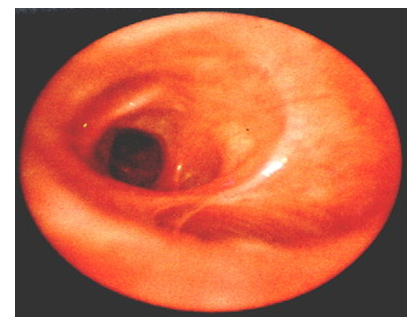

So, due to the original design of the low pressure cuff, high volume and resistant to nitrous oxide, after it is inflated, tight folds of all folds of the mucous membrane of the trachea are achieved, creating a really tight barrier and minimally affecting the mucous membrane of the trachea. When monitoring the pressure in the cuff, the risk of aspiration of the discharge decreases, and as a result of the development of many post-intubation complications.It should be noted that such technical characteristics of these devices as the use of thermoplastic polyvinylchloroethylene with a radiopaque line and anatomical bending angle of the tube - 105°, as well as an open "window" for easy control of the tracheostomy. The floating design of attaching the fixing flange to the tube does not interfere with the displacements of the proximal end of the tube in the transverse direction, and the obturator with an internal channel allows the tubes to be replaced along the guidewire, which reduces the likelihood of stoma injury during insertion of the tube.We used this type of tracheostomy tubes in 8 patients on PMV due to the development of multiple organ failure in the early postoperative period. Three patients were decanulated on the 5th day after the installation of the tracheostomy, two patients on the 10th day and three patients were discharged home on their own breathing through the tracheostomy tube. The endophoto (Fig. 13 and 14) of the condition of the tracheal mucosa after decanulation in patients on the 5th and 15th day after the tracheostomy are presented below. | Figure 13. Tracheal mucosa after decanulation of the Blue Line Ultra tube with the Soft-Seal cuff 5 days after PDT. Catarrhal endotracheitis |

| Figure 14. The mucous membrane of the trachea after the decanulation of the Blue Line Ultra tube with the Soft-Seal cuff 15 days after PDT. The picture of single small-point erosion on the background of catarrhal endotracheitis |